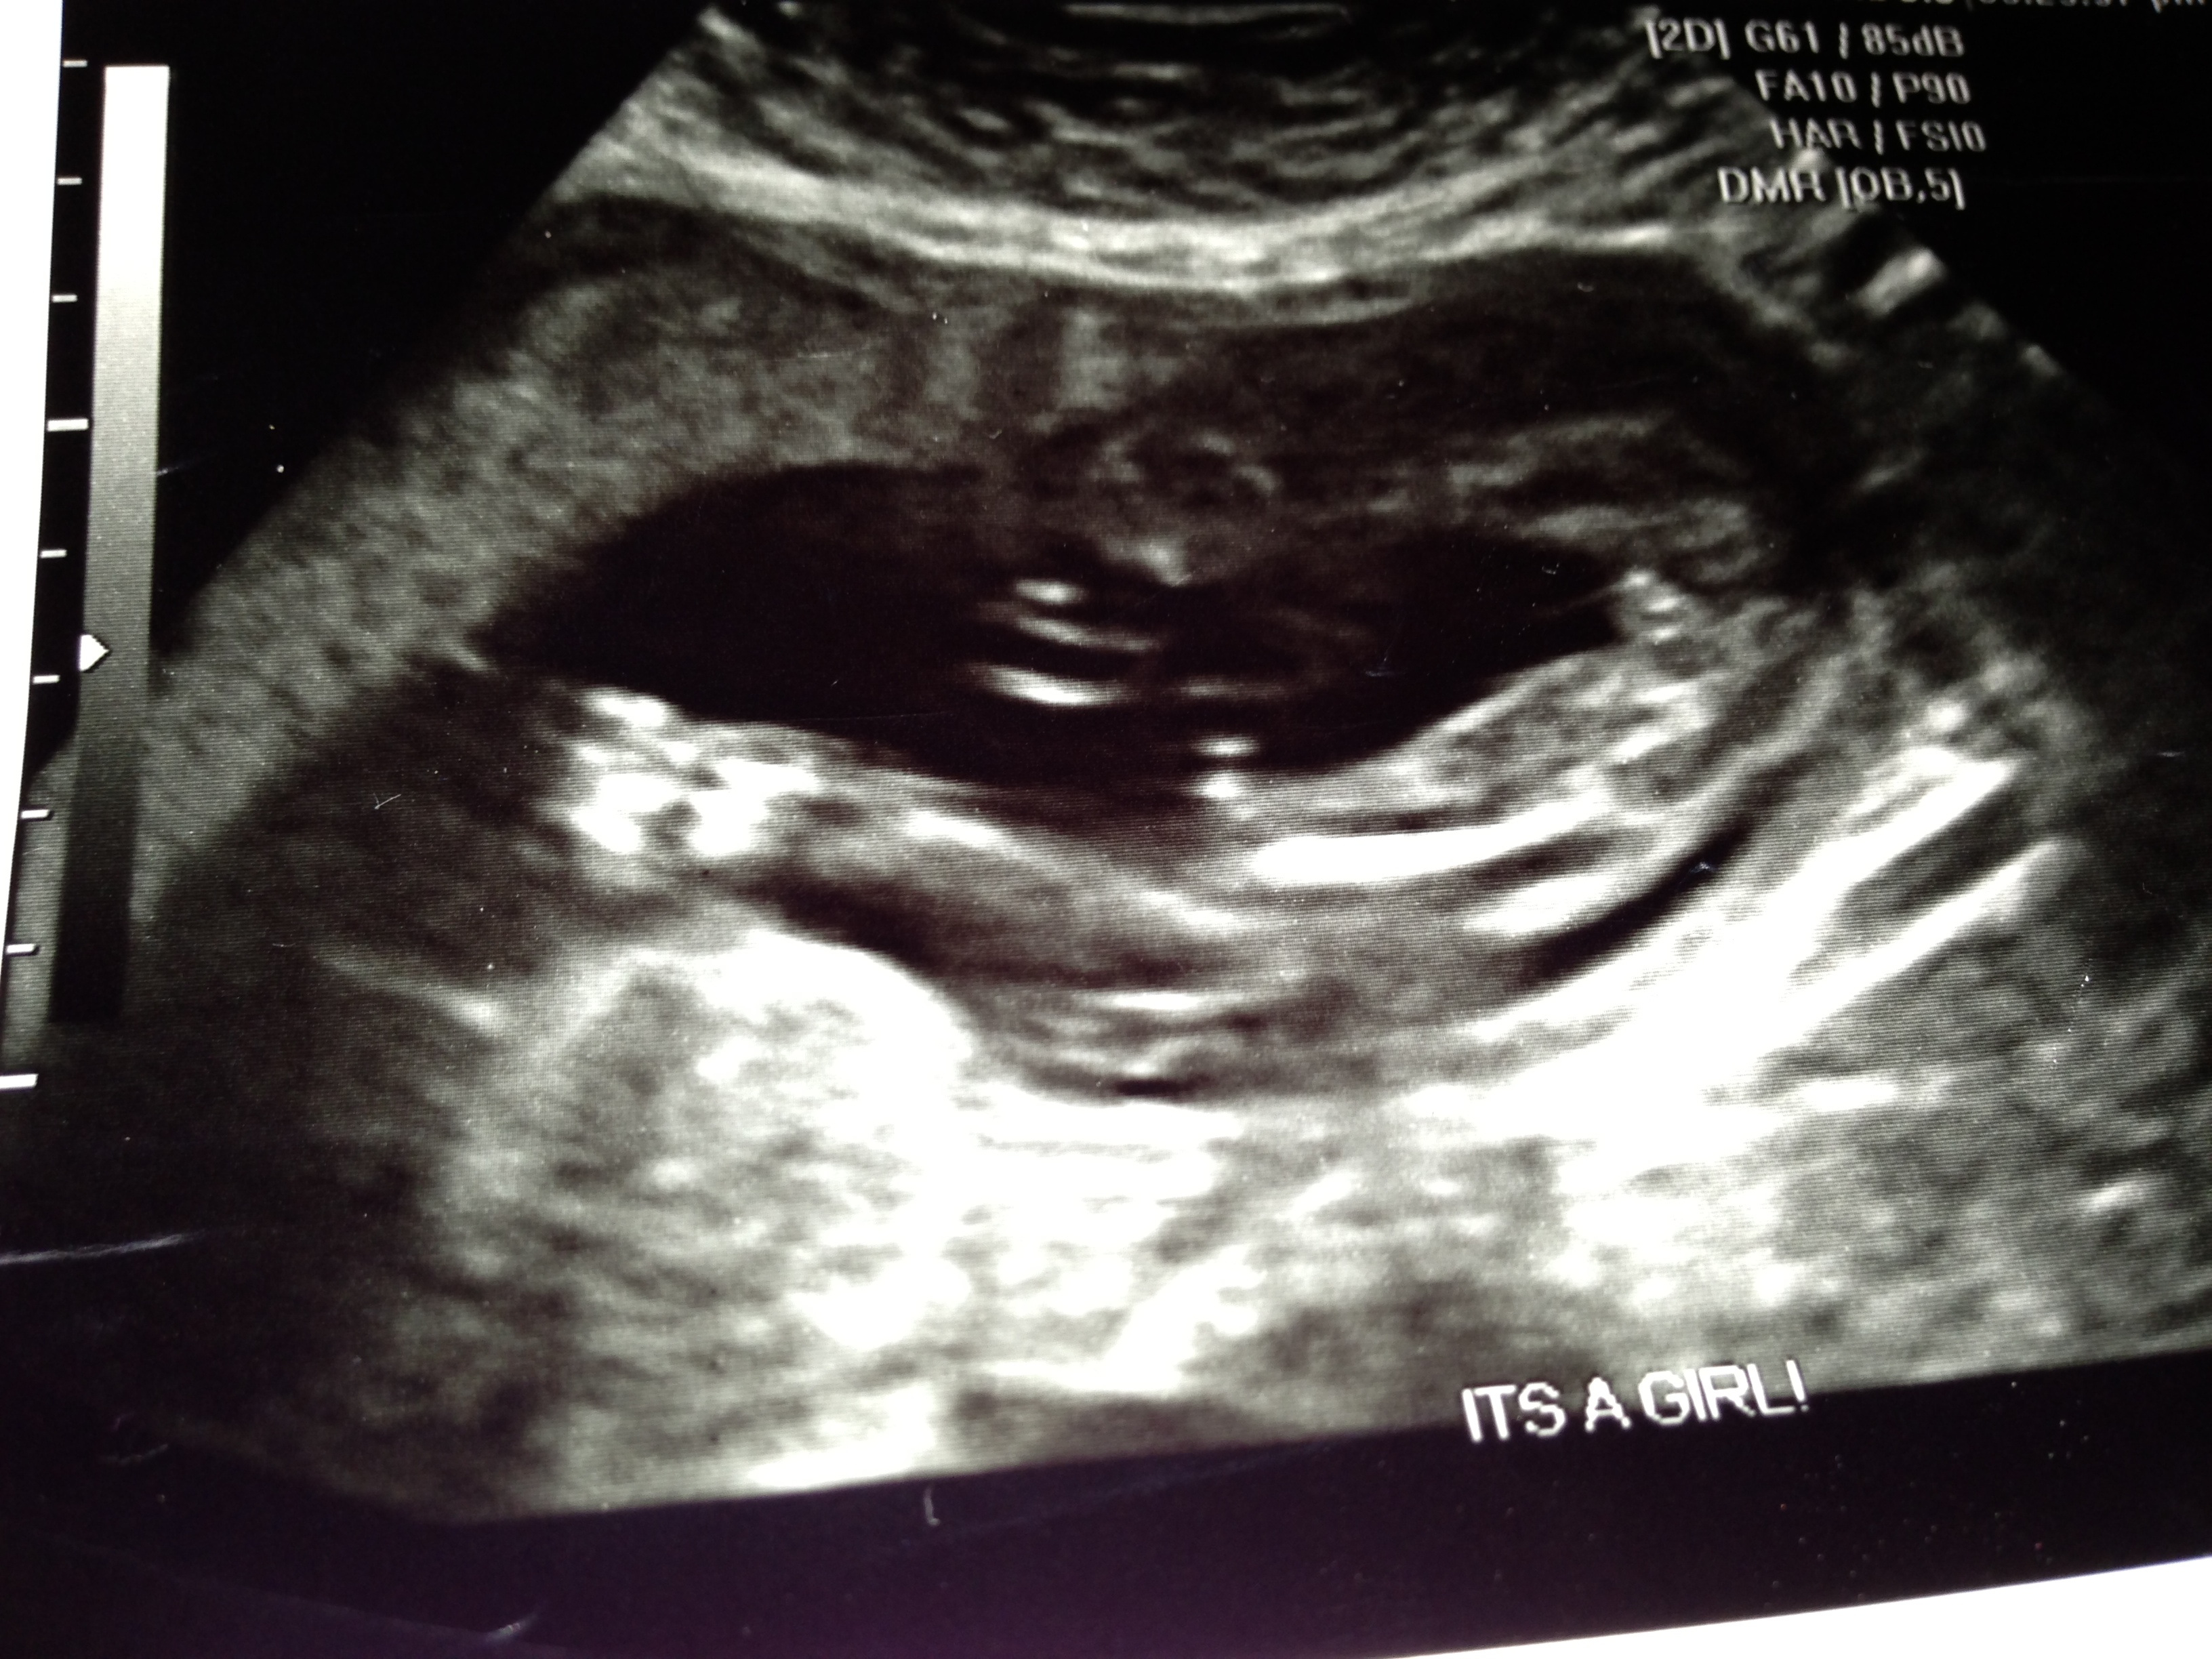

We had ultrasound scanning @ 21 weeks and tech told us its a girl but not 100% sure.

please help us to find out the gender.

Its a girl :-)

if im looking at it right yes it would appear to be a girl......

yeah girl.. 3 lines between legs x